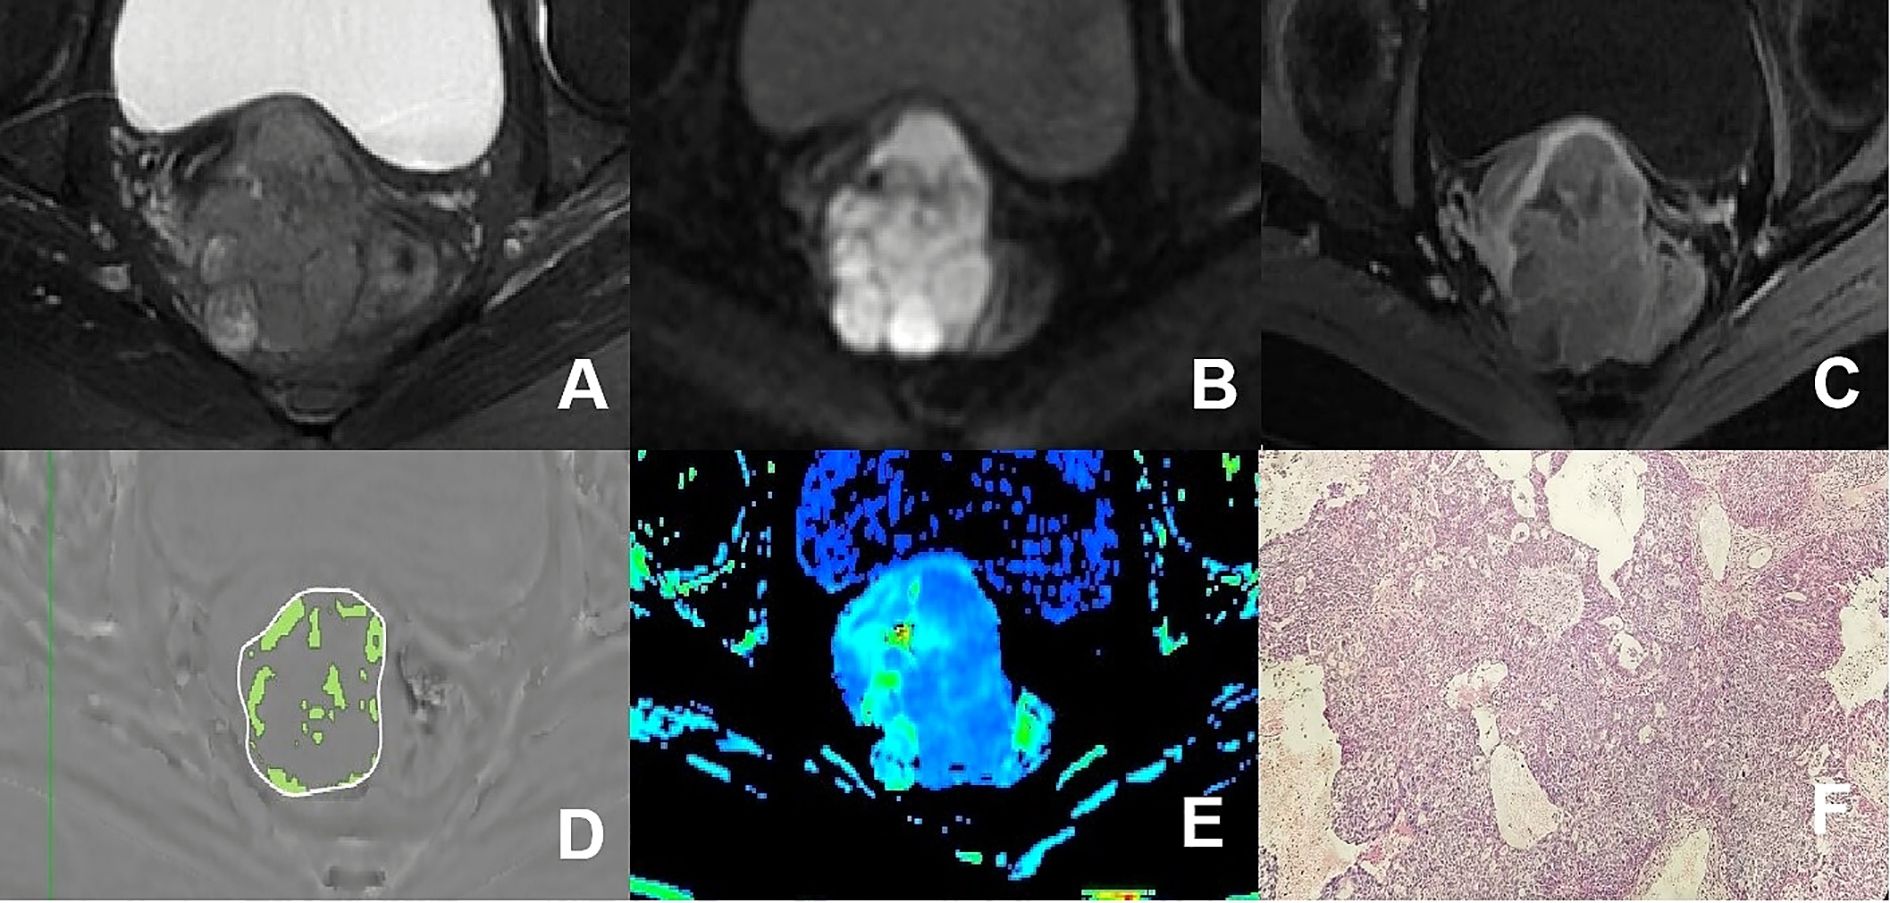

Figure 4

A group of medical images labeled A to F. Image A is an MRI scan showing a large mass. Image B is a close-up of the mass. Image C shows a different perspective of the mass. Image D is a gray-scale image with a highlighted area. Image E displays a color-coded map of the mass. Image F is a histological slide in pink and purple, showing tissue structure.

Figure 4. (A–F) presented a 66-year-old patient diagnosed with poorly differentiated CSC, classified as FIGO stage IIA. (A) Axial T2WI image: the mass presented isointense signal; (B) Axial DWI image: the mass with restricted diffusion exhibited significant hyperintense signal; (C) Axial enhanced image of the delayed period: the mass displayed low level of enhancement; (D) The schematic diagram illustrated the ITSS intensity measured using AS software, where the green area on the diagram signified the ITSS within the tumor, with an ITSSs of 0.091 and ITSSv of 0.077; (E) R2* map of the ESWAN sequence, where the mean value of R2* for this patient was 10.440Hz. (F) Pathological image confirmed CSC.